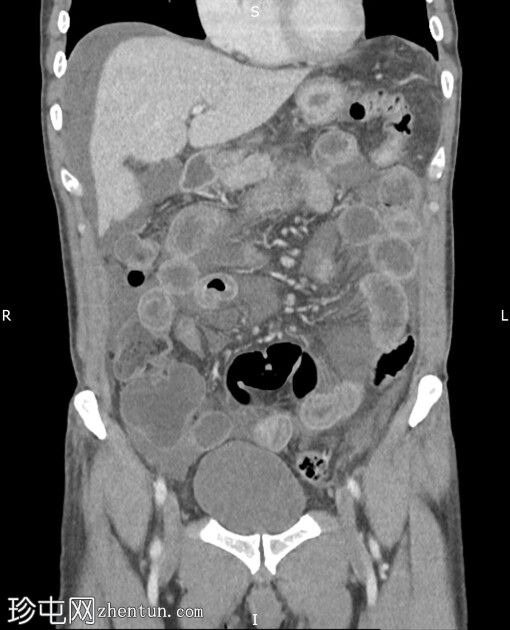

冠状位增强扫描(门静脉期)

小肠袢普遍扩张,无明显移行点。小肠壁弥漫性水肿,提示潜在的炎症改变。腹主动脉及其主要分支通畅,未见血栓或明显的动脉粥样硬化病变。腹盆腔内有大量游离液体。未见肠穿孔。大肠外观正常。腹盆腔内未见明显肿大的淋巴结。

小肠弥漫性水肿。影像表现无特异性,鉴别诊断包括感染、炎症以及(可能性较小)缺血性病变。

随后发现该患者患有C1酯酶抑制剂缺乏症,符合遗传性血管性水肿的诊断。这种疾病是导致此类症状的罕见原因,当患者接受标准治疗方案后症状未见改善时,应将其纳入鉴别诊断。

医生为该患者处方了伊卡替班(一种缓激肽B2受体拮抗剂),用于急性发作期。